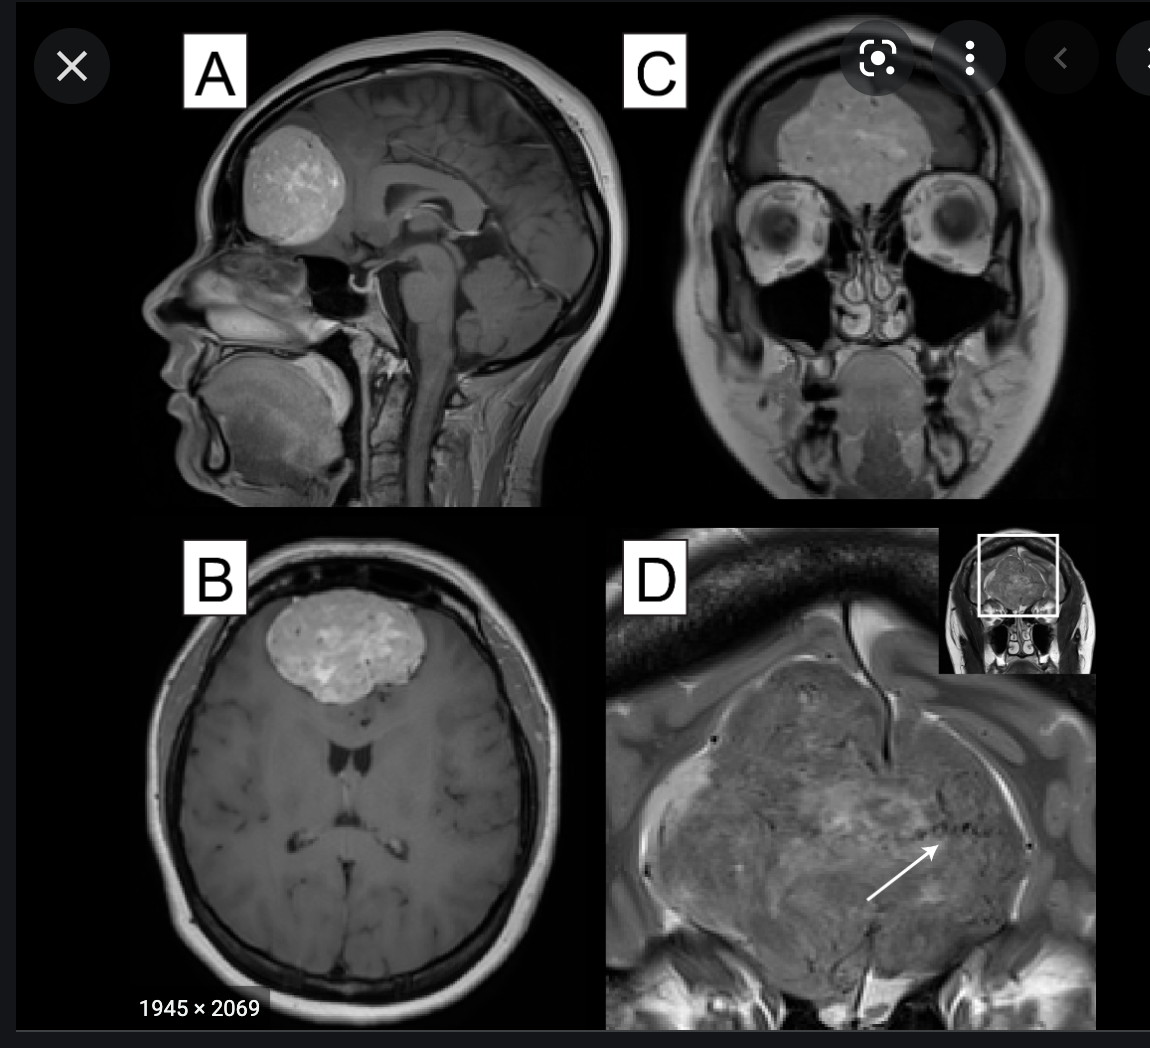

Figure 2: Medial sphenoid wing meningiomas can present different set of technical challenges based on their involvement of the medial neurovascular structures and the encasement of the carotid artery’s perforating vessels. A medial sphenoid wing meningioma with minimal medial extension is shown (upper images). The Sylvian middle cerebral artery branches drape over the superior pole of the tumor. A more true medial sphenoid wing/clinoidal meningioma with significant medial extension and encasement of the ICA is also included (lower images).